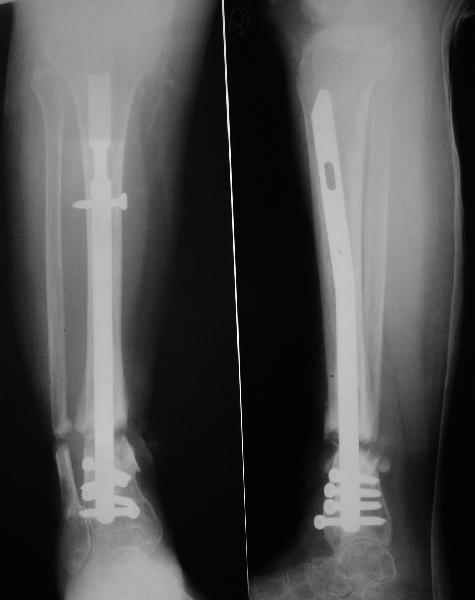

Аппарат - чтобы плавно исправить ось. В приложении - снимки на момент окончания коррекции в аппарате, фото с операции, и послеоперационная рентгенограмма.

Диаметр гвоздика 10,5 мм. Пришлось укорачивать до 23 см - уж очень миниатюрная дама, отверстия насверлил под 45 градусов, под 5 мм винты. По оси удалось сблизить до этого положения. Заперли гвоздь пока статически с планом через 2 месяца верхний винт убрать. Но это ей придется уже в Ташкенте сделать. Что скажете? Спасибо.

In attachment - x-rays at the end of alignment, the surgery, and result. The nail was cut to 23 cm. Four 45 degree holes were pre-drilled at the distal nail tip. The nail was locked statically

after some impaction. Dynamization is considered in 8 weeks. Any comments/critics?